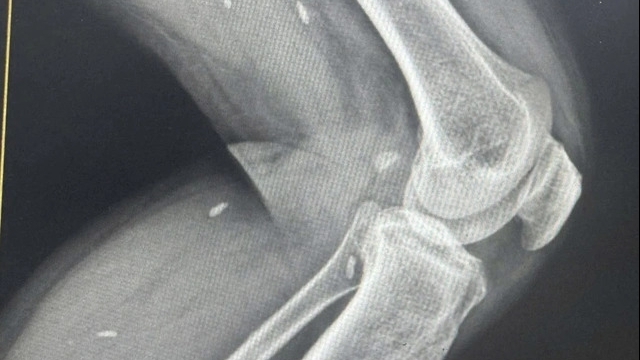

Mổ ruột thừa cấp cứu cho bệnh nhân nữ 28 tuổi trong khu cách ly

Khi đang cách ly, bệnh nhân có dấu hiệu đau bụng. sốt cao trên 38 độ liên tục. Các bác sĩ phát hiện bệnh nhân có phản ứng thành bụng, chụp CT scanner phát hiện có áp xe ruột thừa trong ổ bụng.

Sau khi hội chẩn, các bác sĩ đã quyết định phẫu thuật cấp cứu cho bệnh nhân. BS. Trần Thượng Việt - Trưởng khoa Ngoại - Sản - người trực tiếp phẫu thuật - cho hay: Bệnh nhân đã cắt xong ruột thừa, dẫn lưu ổ áp xe ra ngoài.

Hiện, bệnh nhân đã phục hồi, sức khỏe ổn định, tiếp tục được theo dõi chặt chẽ tại bệnh viện.

Ngay từ những ngày đầu chống dịch Covid-19 , Bệnh viện Bệnh nhiệt đới Trung ương đã chuẩn bị sẵn sàng các ekip phẫu thuật cấp cứu tiêu hóa, tiết niệu, chấn thương và sản khoa cùng toàn bộ đồ bảo hộ để phục vụ các bệnh nhân trong thời gian cách ly cần phẫu thuật cấp cứu.